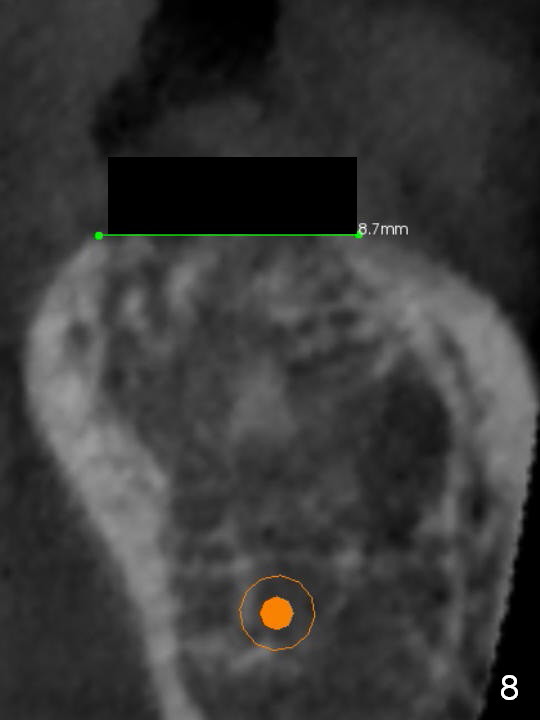

Preop palpation of the edentulous area at #18 does not show the flatness of the ridge top as shown by CBCT.  Incision reveals that the ridge is not as wide as CBCT indicates (Fig.1 (coronal section) between arrowheads).  In fact the ridge is concave (Fig.2 red dashed line).  Osteotomy is initiated in the middle of the concavity (Fig.2 green line) with insertion of 7 mm guide pin (Fig.3).   After removal of the pin, the osteotomy is moved buccally (Fig.4).  After Marking Bur and 4.3 mm Magic Drill, a 5x9 mm IBS implant is placed with 2.8 mm clearance from the Inferior Alveolar Canal (Fig.6).  Following deepening the osteotomy with Final Drill, the implant is placed deeper (Fig.7).  The osteotomy happens to be established in the mesial socket, since the distal socket has not completely healed (Fig.6 yellow dashed line).  Granulation tissue is removed.  Since the lingual crest is lower than the buccal one (Fig.1 B), there is lingual thread exposure after implant placement (Fig.5).  The exposed thread is covered by bone graft (autogenous bone, allograft and Osteogen, Fig.5 pink circles).  Some of the graft is apparently pushed into the distal socket (Fig.7 yellow dashed line) post GBR and suture.  As the implant is placed twice, insertion torque is <10 Ncm (although the implant is stable).  A 5x3 mm healing abutment is placed (Fig.7 H).

To bury the implant evenly, the ridge should be flattened (Fig.8) prior to osteotomy and implant placement (Fig.9) when bone height is sufficient.